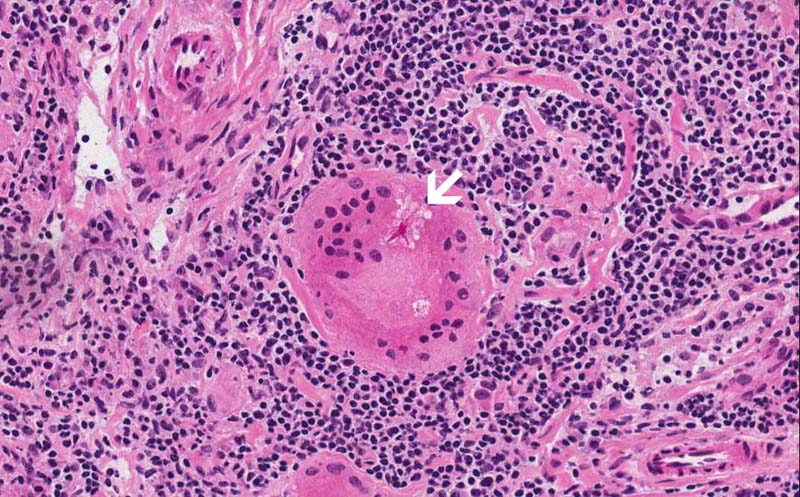

Area 1: Granulomas (arrow) are collections of histiocytes. These cells will be strongly reactive for antibody against CD68 or CD163 which mark histiocytes. Immunohistochemistry is useful when the granuloma is not as well defined or if there is a question that these cells may represent metastatic carcinoma. Granulomas in sarcoidosis is usually free of necrosis. Typically, they are not infiltrated by a substantial amount of lymphocytes and they are quite well defined from the surrounding lymphocytes. They also are more likely to be round or oval. In contrast, granulomas in tuberculosis are usually infiltrated by lymphocytes, much less well defined, more irregular in shape, and may have caseous necrosis.

• The salient histopathologic change is the replacement of the entire lymph node by non-necortizing granuloma (Area 1). Lymphocytes are present in between the granulomas. On examination with polarized light, no birefringent substances are present.

• Granulomas are roughly round to oval to irregular collections of histiocytes often with mutinucleated giant cells. They can be seen in multiple types of disease processes that include sarcoidosis, fungal infection, mycobacterial infections, berylliosis, foreign body, granulomatous changes of neoplasms particularly lymphomas and germ cell tumors, Wegerner's granulomatosis, and other conditions.Granulomatosis in sarcoidosis is usually non-necrotizing but necrosis may occur. Inclusions such as Asteroid bodies (Area 2) and Schaumann bodies can be seen in sarcoidosis. These inclusions are suggestive, however, non-diagnostic for sarcoidosis.